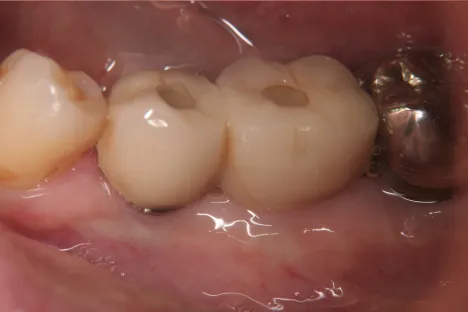

Dr.-Taniguchi_Fig.7

Fig. 7. Approximately one year after bone regeneration treatment: No inflammation was observed in the surrounding tissue.